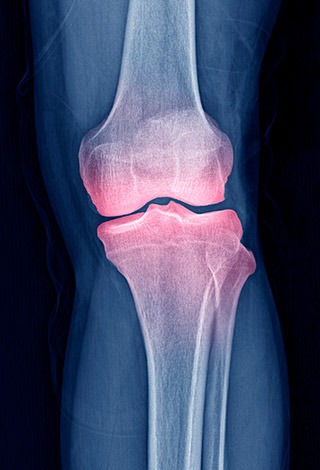

Inside every healthy joint is a thick, gel-like fluid called synovial fluid — often nicknamed “joint jello.” Its job is to cushion, lubricate, and protect your joints.

As we age, this joint jello can thin and dry out. When that happens, joints lose their smooth glide — leading to stiffness, inflammation, and painful grinding.